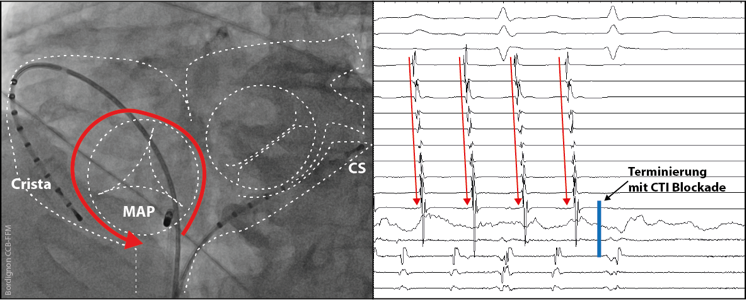

typ-vorhofflattern

(Abb. 2) Typische Katheterpositionen bei der Ablation von typischen Vorhofflattern (links). Unter Anlage einer sogenannten cavo-trikuspidalen Isthmuslinie im rechten Vorhof erfolgreiche Terminierung der Tachykardie in Sinusrhythmus (rechts).